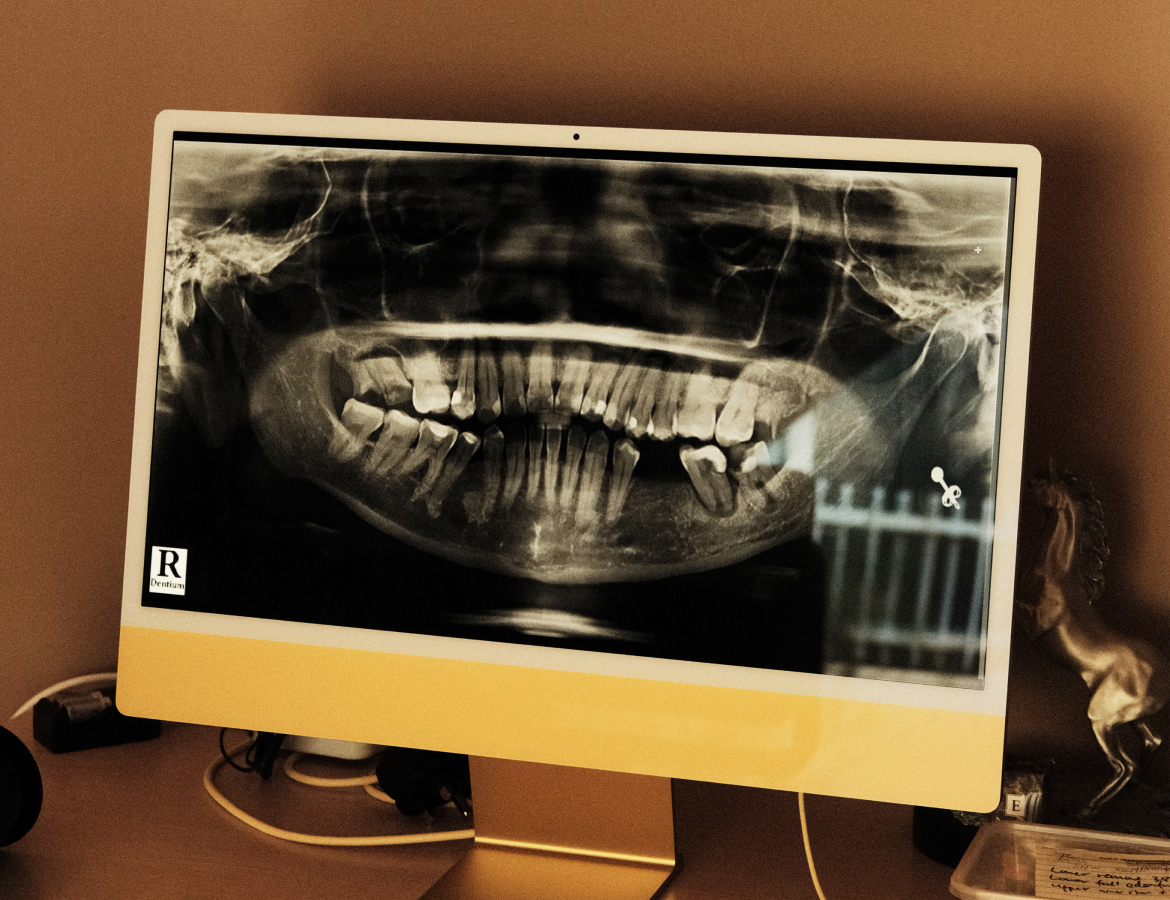

CT Scan and Individualized Surgery Treatment Plan

We will run a CT scan to get an in-depth analysis of your teeth. The data collected are imported into the digital implant planning software and a virtual surgery treatment plan will be proposed.

Carrying Out Surgery and Digital X-Ray

Once the customer approve the proposed treatment plan, we will proceed with the surgery based on the plan created with the digital software.

Accurate and guided implant treatment will then be followed for a worry-free process.